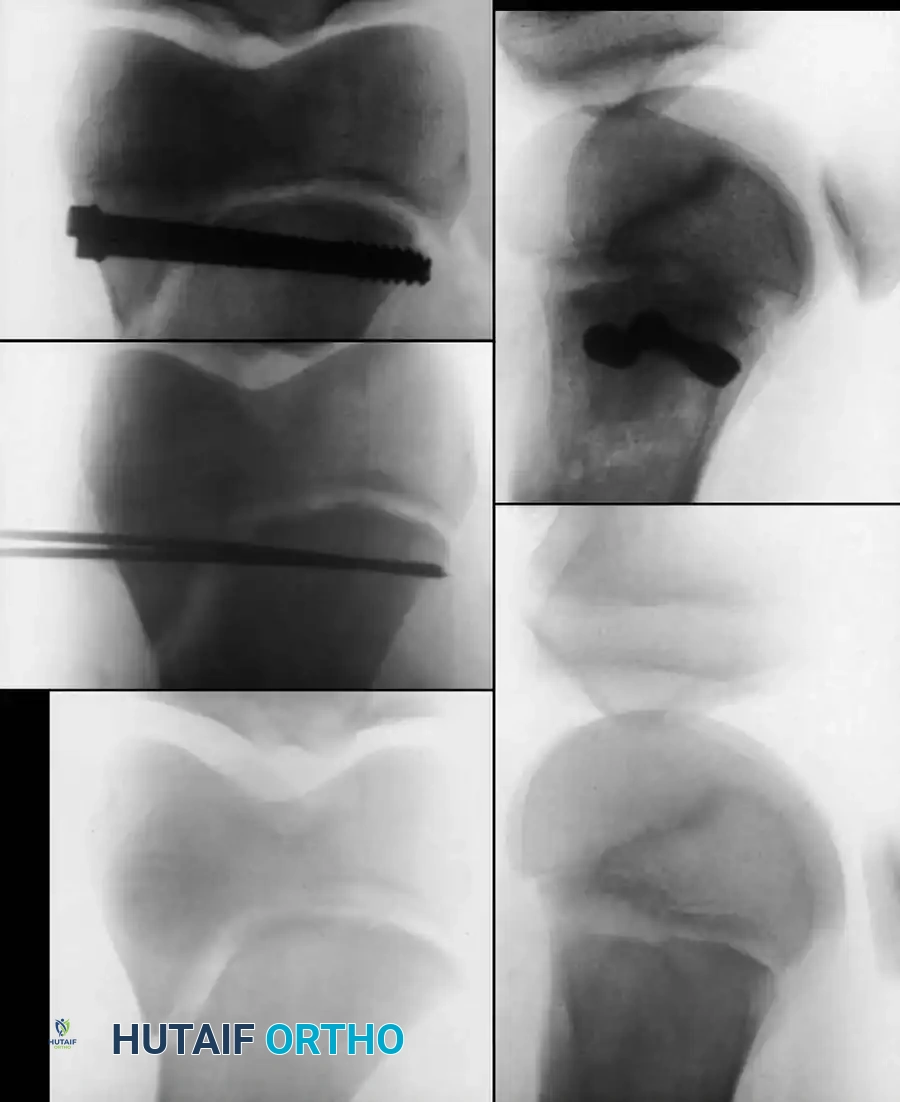

DISTAL FEMORAL PHYSEAL AND SUPRACONDYLAR FRACTURES

Fractures involving the distal femoral physis (Salter-Harris types) or the supracondylar region require distinct management. The distal femoral physis contributes 70% of the growth of the femur and 40% of the overall growth of the lower extremity. Consequently, anatomic reduction is paramount to minimize the risk of premature physeal closure and subsequent limb-length discrepancy or angular deformity.

AP radiograph demonstrating a displaced Salter-Harris II fracture of the distal femur.

Intraoperative fluoroscopy showing smooth Kirschner wire fixation crossing the physis to stabilize a Salter-Harris fracture.

Cannulated screw fixation of a distal femoral epiphyseal/metaphyseal injury, ensuring the threads do not cross the open physis.